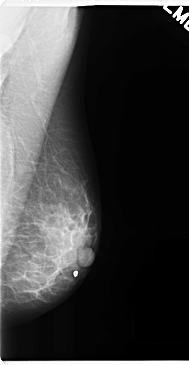

C_0270_1.LEFT_MLO

LEFT_MLO LINES 4736 PIXELS_PER_LINE 2456 BITS_PER_PIXEL 12 RESOLUTION 50 NON_OVERLAY